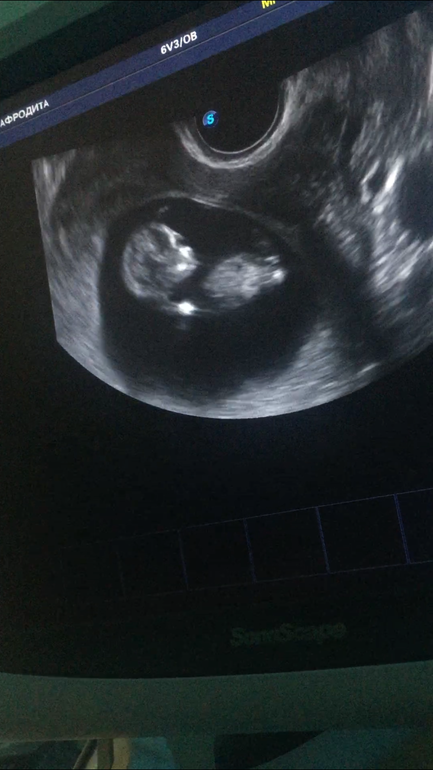

Девочки, многие тут шарят.Заливаю два фото, хочу послушать Ваши мнения кто есть кто?Тем самым сравню слова узиста))Срок у обеих фотографий один

Узист мне тоже сказала девочка)) но как почитала, что на таких сроках ошибаются)) Решила тут спросить))